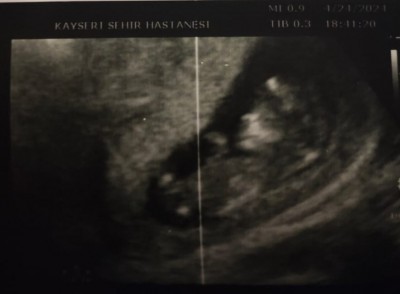

26 Nisan 2024 Hamilelikte Testler kategorisinde (12 puan) sordu

Bu görüntüyle tahminde bulunabilecek arkadaşlar varmı :))

Gebelik haftası 12

Canım benim öncelikle o çocuk normal yatıyor cinsiyet tahmini doktorlar bacak arasına bakarlar burda imkanı yok kimse sana kız erkek demez diyemez burası hastane değil doktor değiliz biz çünkü

Muhtemelen erkek söylentilere göre hem sağda hem çenesi uzun hemde kesesi fasulye gibi  erkek dyorlar